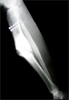

Pre

Op

▪ 33 years old man with open fracture tibia.

Initially treated with debridement ,

interfragmentary screws and external fixator

▪ Cast applied after EF removal and fracture

displaced after three months

▪ Presented with malunion tibia (deformity and shortening)